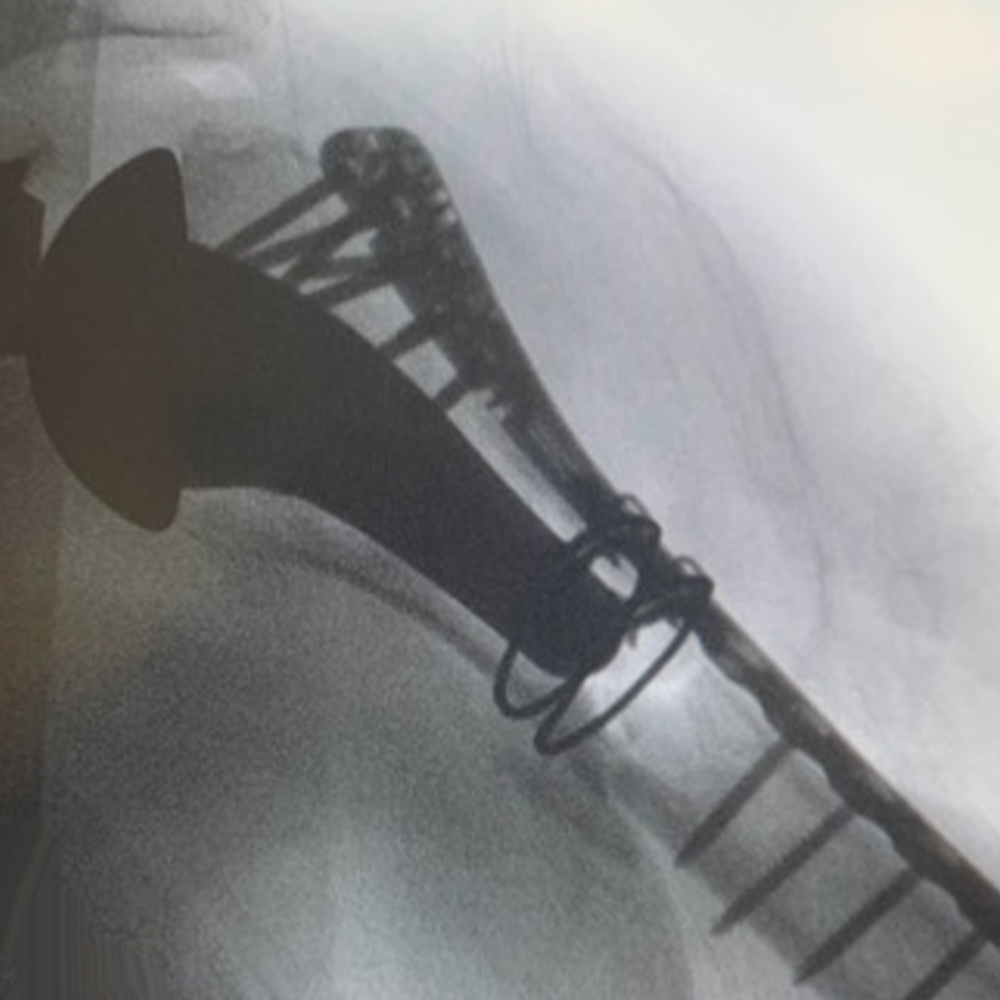

Periprosthetic Solutions

PLATING SYSTEM

- Only UE plating option that allows each same hole for:

- Screw placement

- Compression

- Screw lock into plate

- Cerclage Capability

- 40° Polyaxial locking

- Strong & consistent locking at every angle

- Titanium low-profile construct

- Compression before locking

- Polyaxial drill guides allow for provisional K-wire fixation